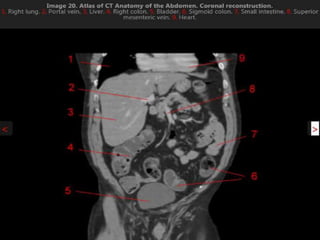

CT cross sectional anatomy.

CT – computedtomography. •Cross-sectional modality with capabilities for multiplanar reconstruction and dynamic imaging to assess vascularity •Tube rotates around the body and a circle of stationary detectors detects the penetrating x-rays forming an image.